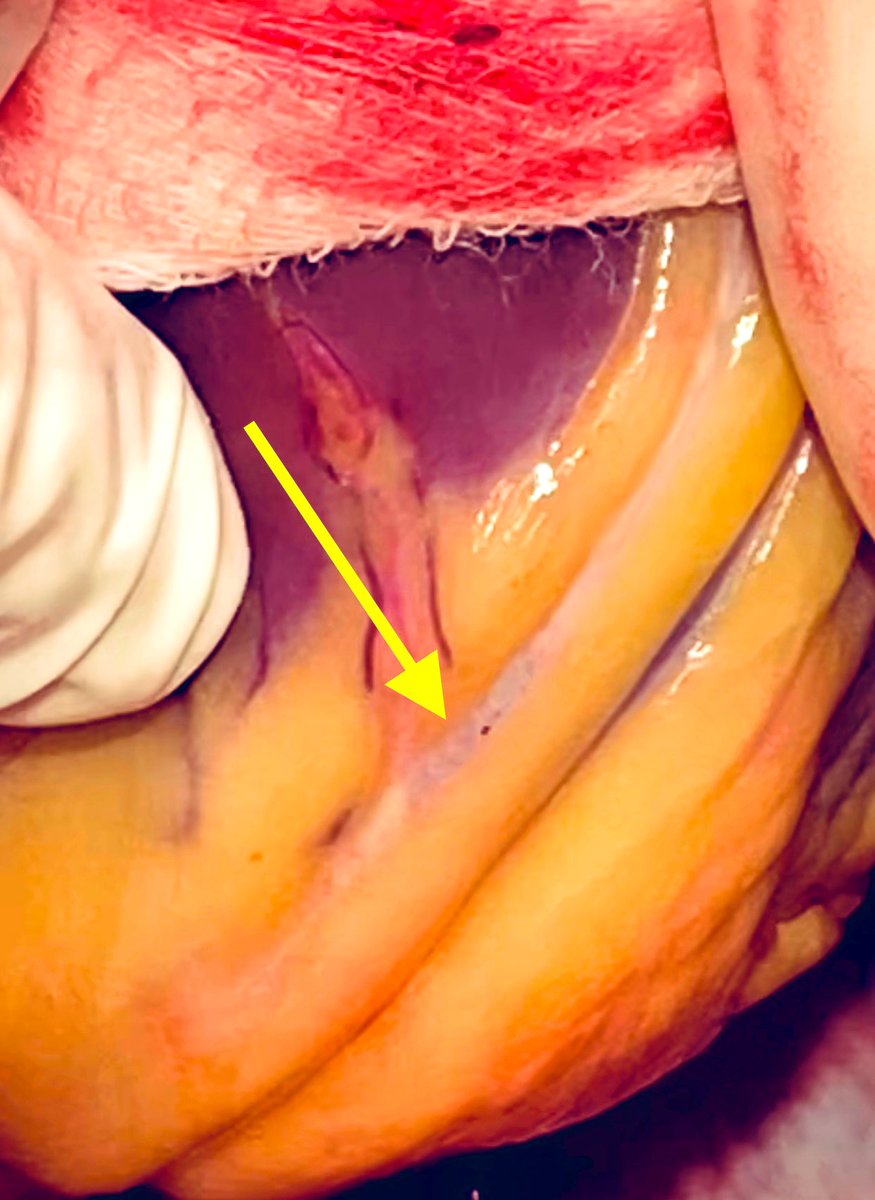

Distal Perfusion catheter placement Tweetorial #UABStructural

@MustafaAhmed , @Mouhamedamr1, @BaranAksutMD , @PhillipASmithMD , @MadhuraMyla @DocEBROhimi

Today: Constrictive pericarditis. Pericardiectomy+ epicardial decortication. Not the nicest procedure, but love the result. @SECTCV @CardioRed1 @secardiologia

139

927

6K